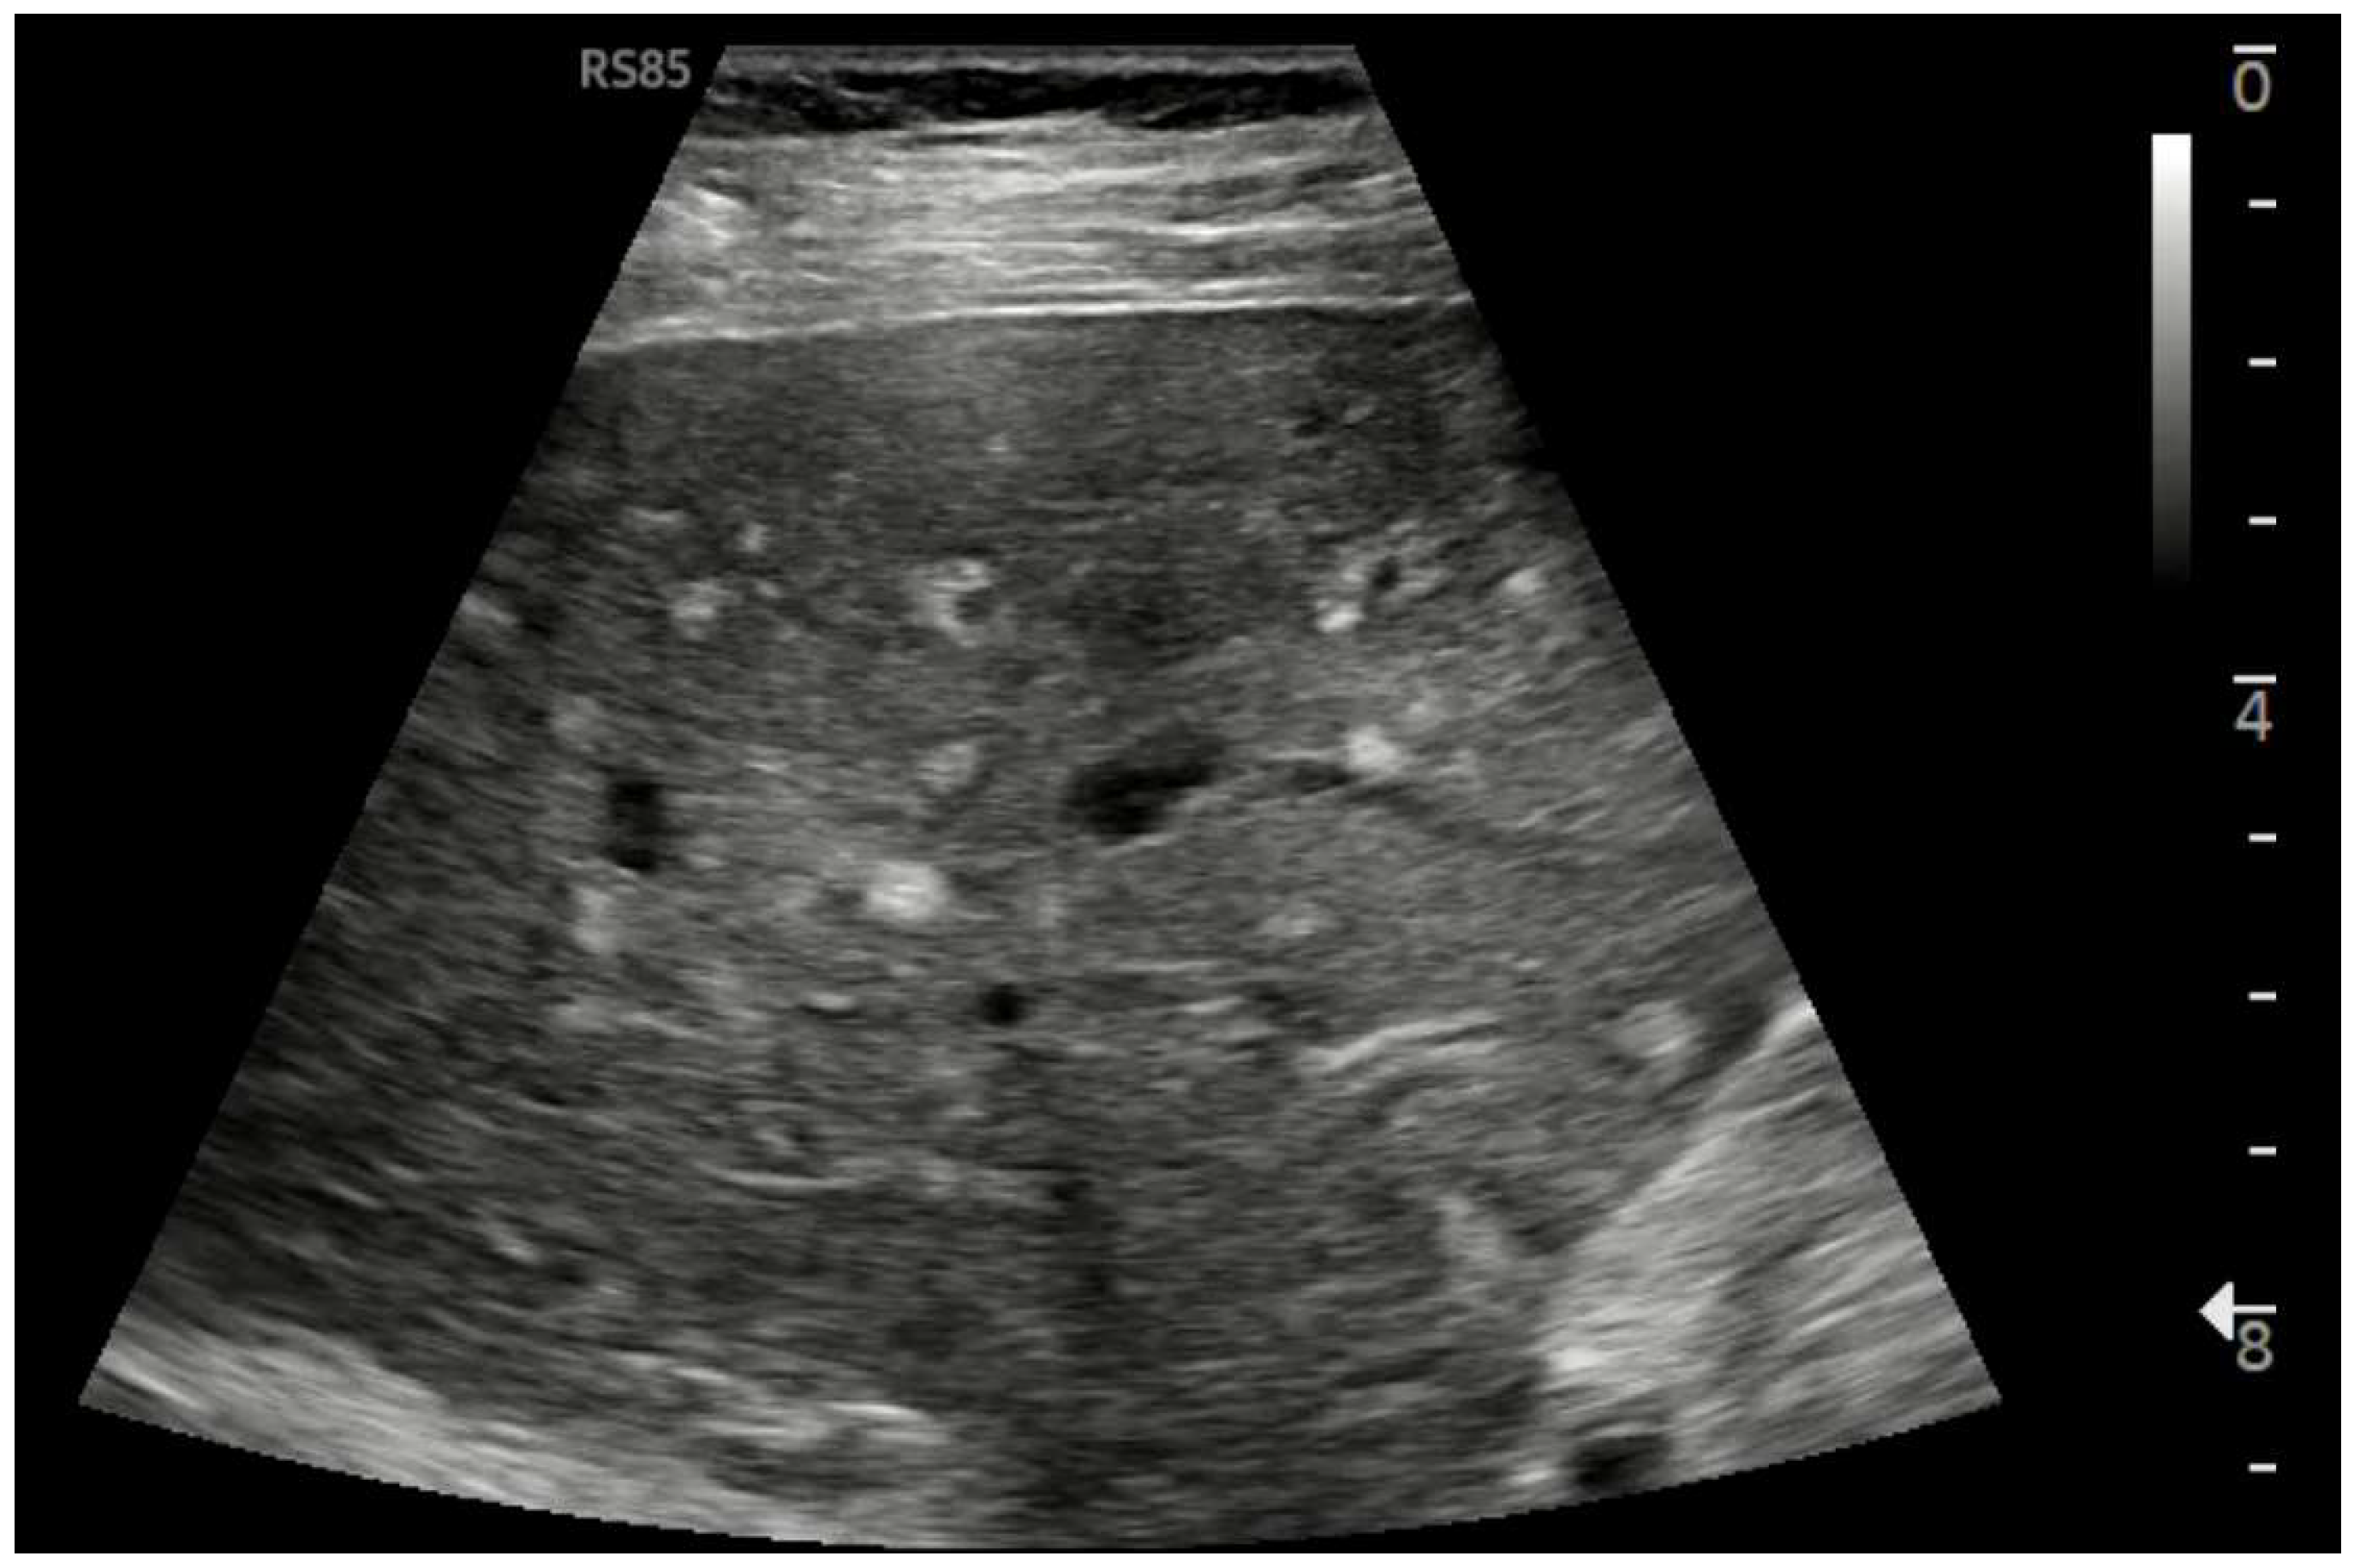

Figure 7.

Hypotrophy of the right lobe. Nodular profiles. Markedly heterogeneous echostructure, with increased fibrous component and fibrous trabeculae delimiting pseudo-nodular areas, within the context of a vascular-type cirrhosis.